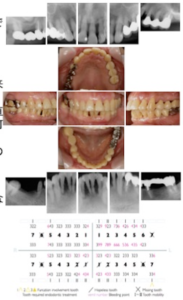

患者:64歳.女性初診日:2003年12月

主訴:右下ブリッジの脱離、歯が磨きにくい歯科既往歴:十数年来

歯科治療を受けていない

現症:全顎的に水平性/垂直性骨吸収.

特に、上顎左側に多くの垂直

性骨損.37歯に根分岐部病変.下顎4前歯は骨欠損が著明で保存不可

能.4mm以上PPD30%,Bop(+)33%.

多数菌における動揺.病的な歯

牙移動

顎位の偏位を疑う、右側犬歯関係1級、左側犬歯関係II級の

咬合関係.

診断名:広汎型重度慢性歯周炎

初診時(2003年12月)